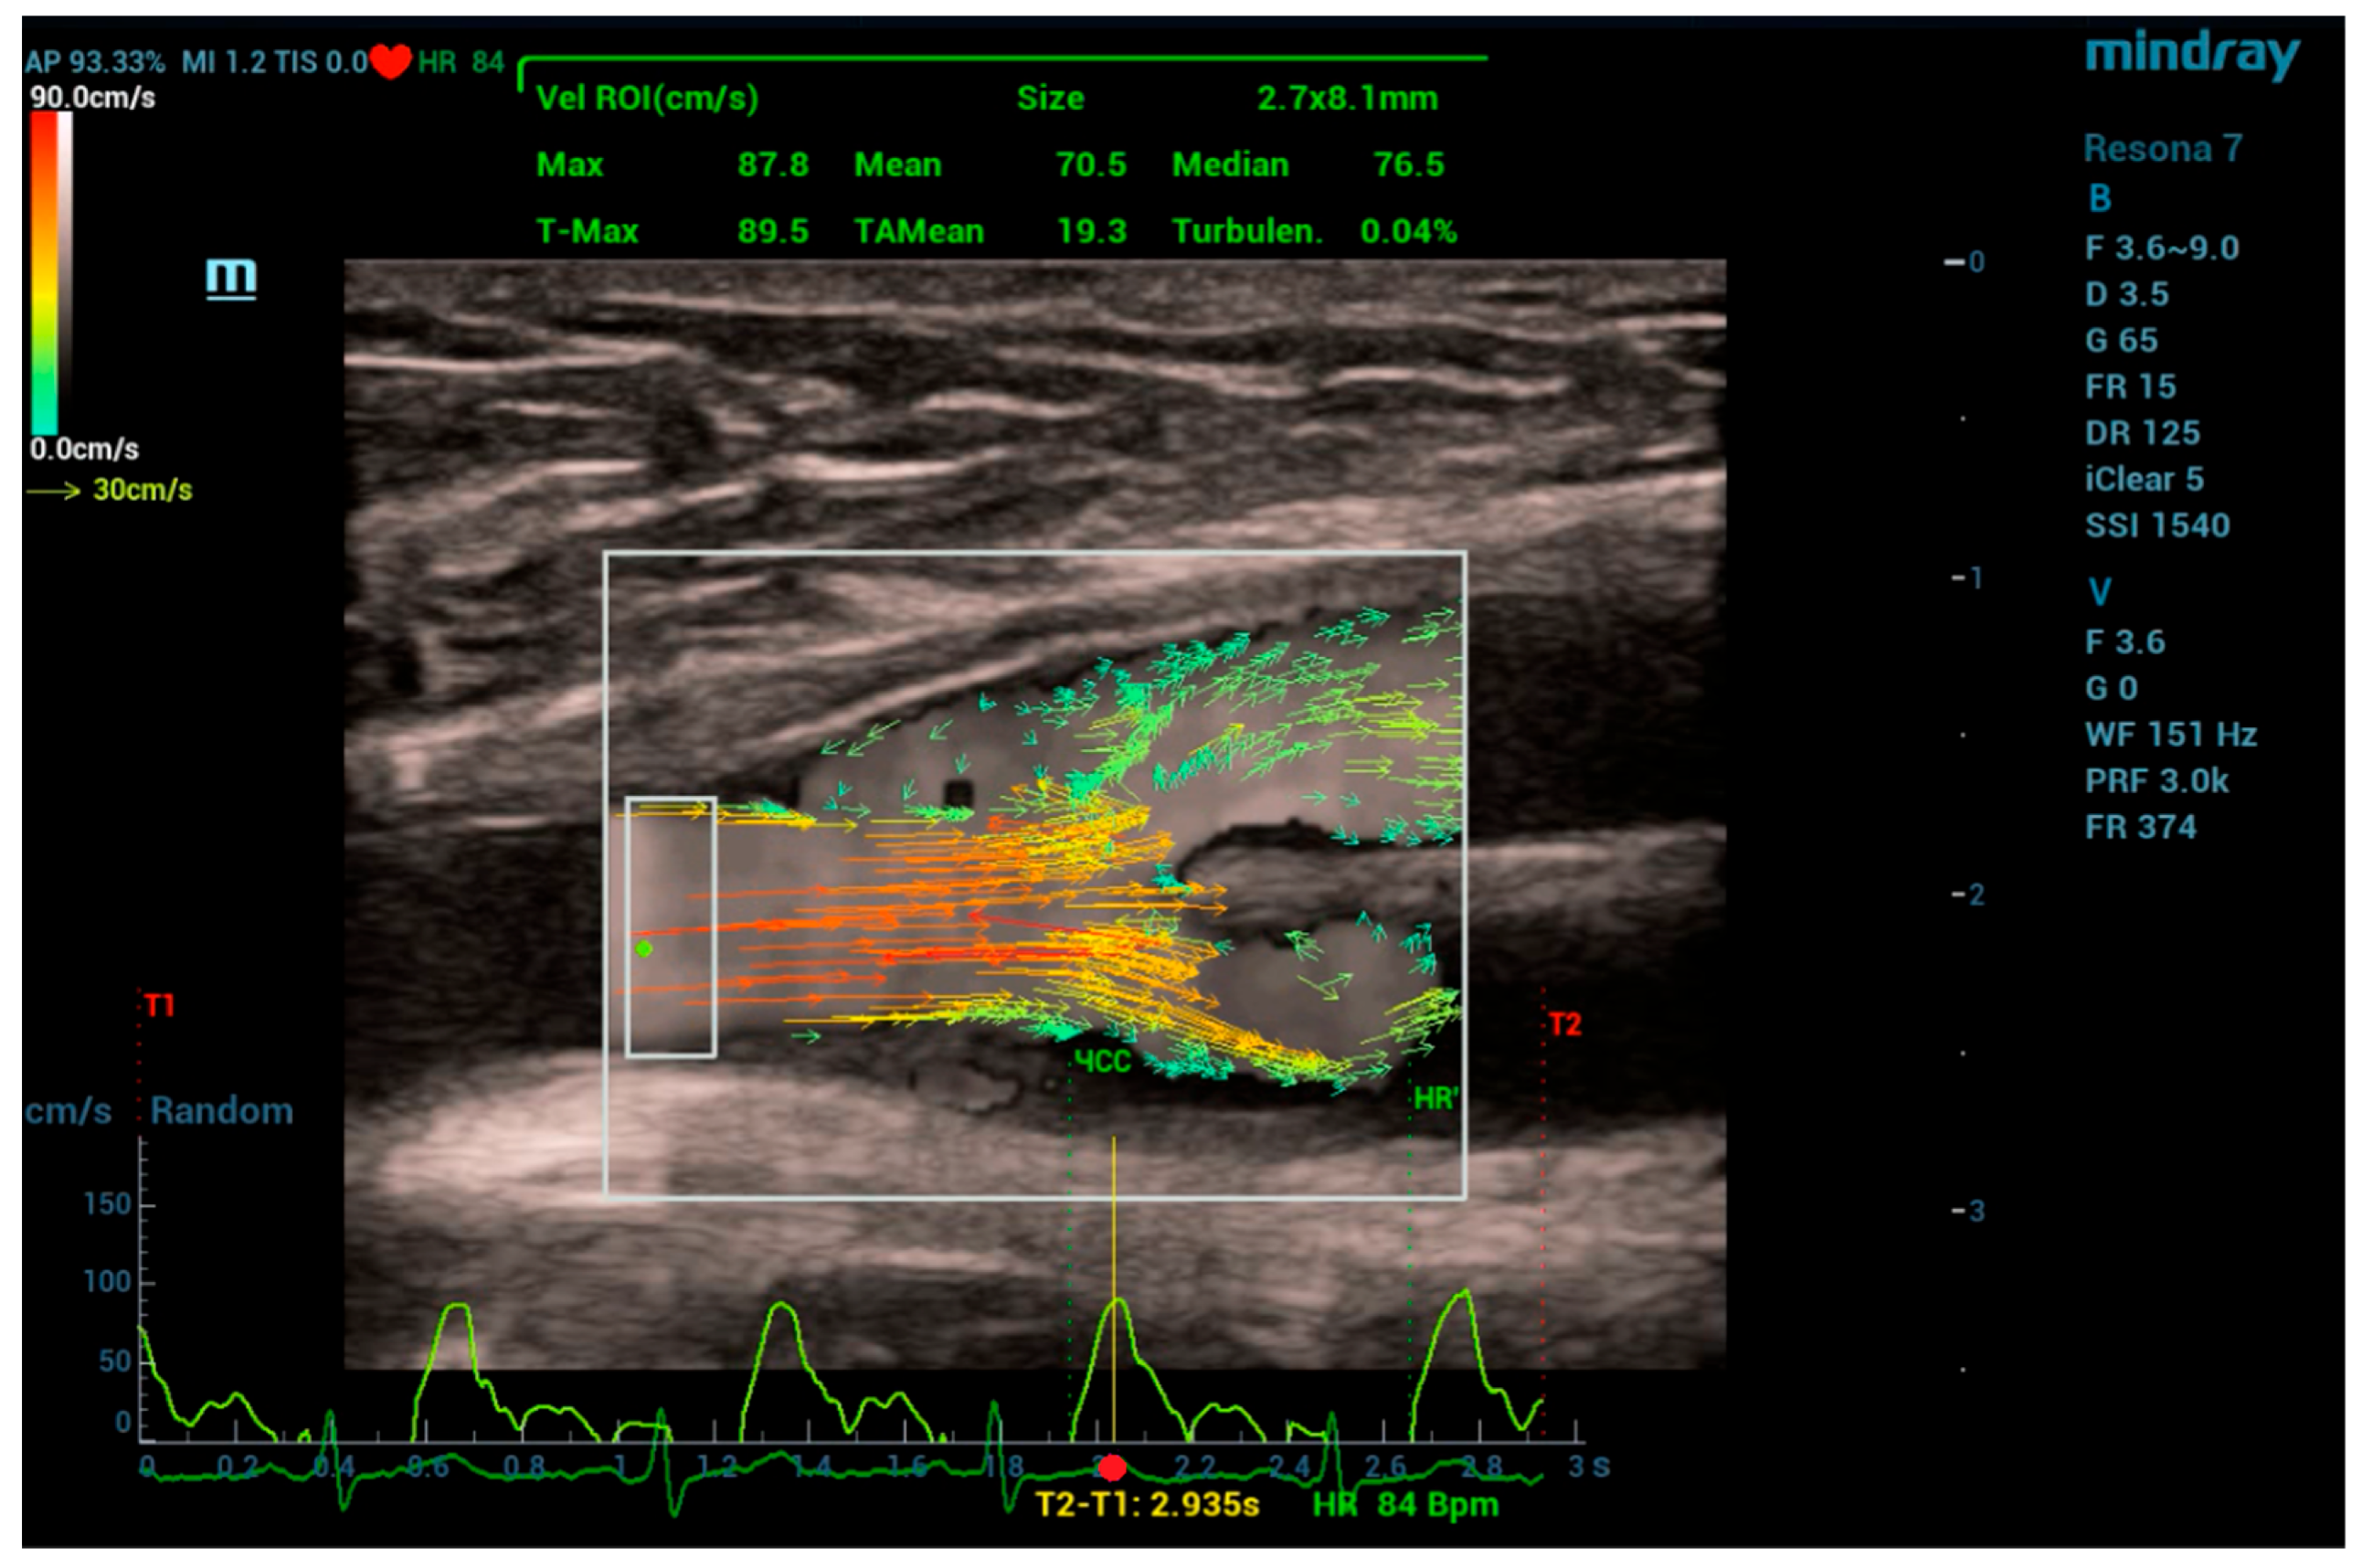

During the measurements, the scanning plane of the ultrasound transducer coincided, as it was possible, with the middle longitudinal plane of the anastomosis areas under examination. Figure 4 shows the window of the V Flow program with a 2D vector velocity field directly at the site of the graft branch from the CFA. Here, the scanning window, highlighted with a white frame, has dimensions of 20 × 27 mm. The results of the vector field processing for the region of interest (ROI), highlighted with a white frame with dimensions of 2.7 × 8.1 mm, are visualized by the velocity curve (light green curve) at the point of maximum velocity in the ROI (green dot), being synchronized with the electrocardiogram signal shown at the window bottom. The upper part of the window displays the values of automatically calculated flow velocities for the ROI. The following notations are used here: Max—instantaneous maximum velocity, T-Max—maximum velocity during recording time (T1~T2), Mean—instantaneous average velocity over ROI, TAMean—average velocity over recording time (T1~T2), Median—instantaneous median velocity, Turbulen—velocity pulsation parameter, and Size—ROI size.

Figure 4. V Flow program window when placing the scanning window at the site of the graft branch from the patient’s common femoral artery.